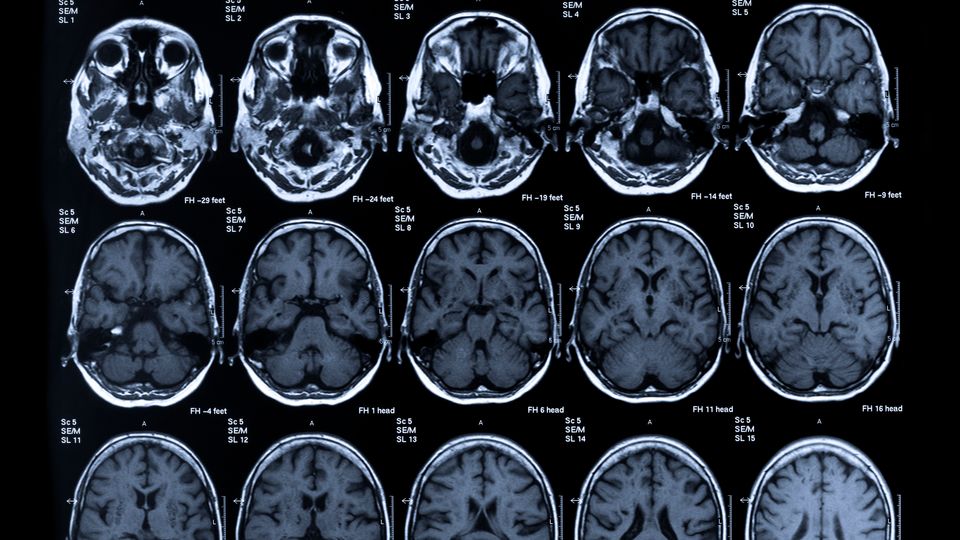

我去医院检查。接下来的几天,不安始终挥之不去。血液检查、X光、CT扫描接连进行。这些检查看起来都再平常不过——直到结果出来,一切彻底改变:垂体肿瘤正压迫着我的视神经。

示意图(图源:网络)

我坐在诊室里,整个人愣住了。医生语气平稳地解释肿瘤情况、肿块效应,以及对视力可能造成的风险。我听见了每一个词,却无法真正消化它们。